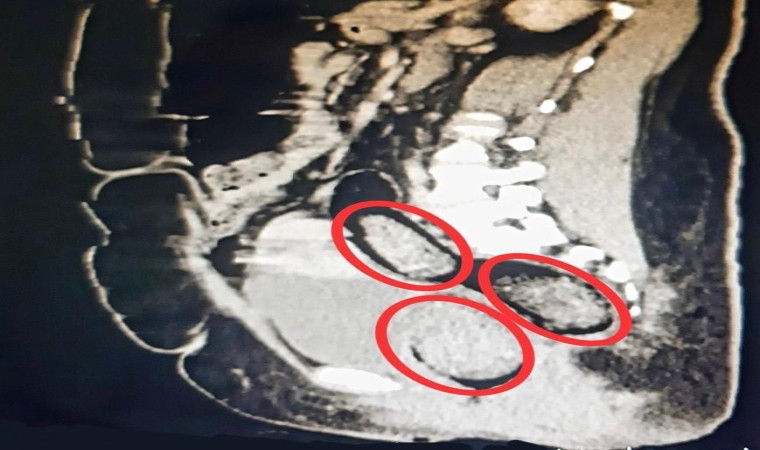

Otobüste gözaltına alınan Hadıs Aeınezad’in yapılan iç beden muayenesinde bağırsaklarında cisim olduğu tespit edildi. Hadıs Aeınezad’ın makadına saklanmış bir şekilde 3 parça 318 gram metamfetamin uyuşturucu maddesi cerrahi müdahaleyle çıkarıldı.